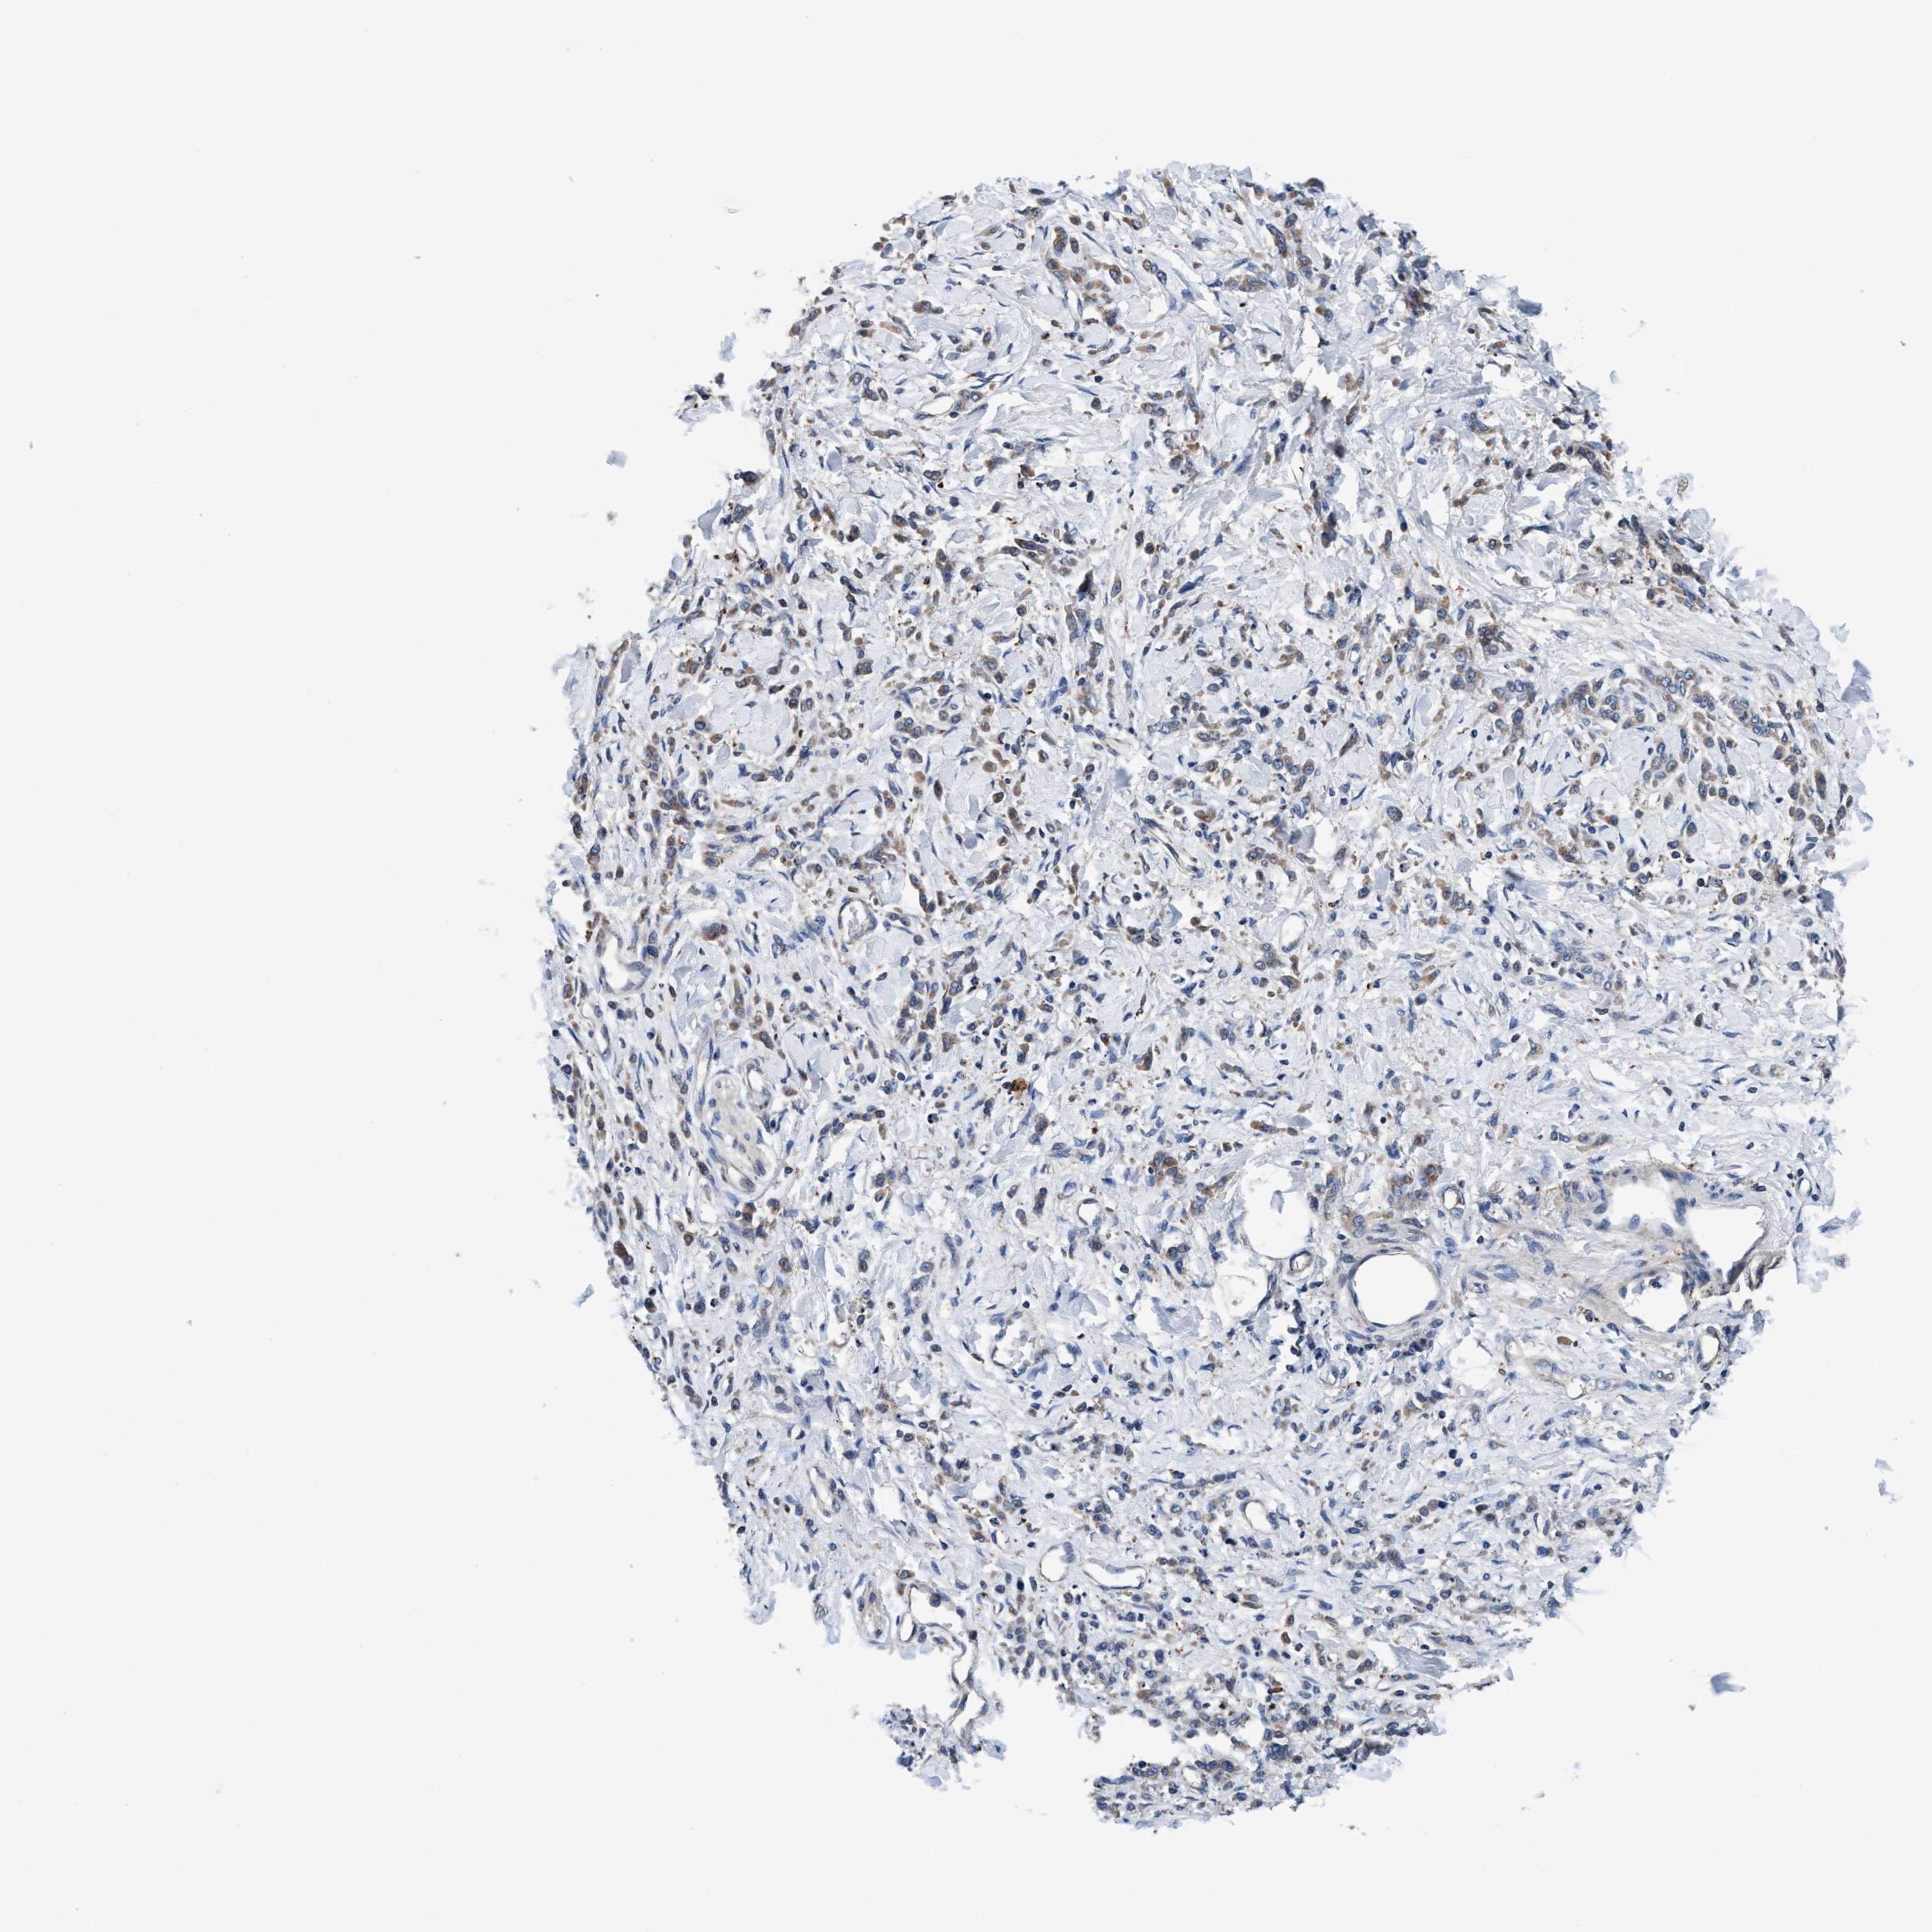

STOMACH CANCER - Protein expressioni

A mouse-over function shows sample information and annotation data. Click on an image to view it in a full screen mode. Samples can be filtered based on level of antibody staining by selecting one or several of the following categories: high, medium, low and not detected. The assay and annotation is described here.

Note that samples used for immunohistochemistry by the Human Protein Atlas do not correspond to samples in the TCGA dataset.

Antibody stainingi

Antibody staining in the annotated cell types in the current human tissue is reported as not detected, low, medium, or high, based on conventional immunohistochemistry profiling in selected tissues. This score is based on the combination of the staining intensity and fraction of stained cells.

Each image is clickable and will lead to virtual microscopy that enables deeper exploration of all samples and also displays staining intensity scores, fraction scores and subcellular localization as well as patient and tissue information for each sample.

Antibody HPA021335

Antibody HPA021830

Staining

High

Medium

Low

Not detected

Intensity

Strong

Moderate

Weak

Negative

Quantity

>75%

75%-25%

<25%

None

Location

Nuclear

Cytoplasmic/membranous

Cytoplasmic/membranous,nuclear

Adenocarcinoma, NOS